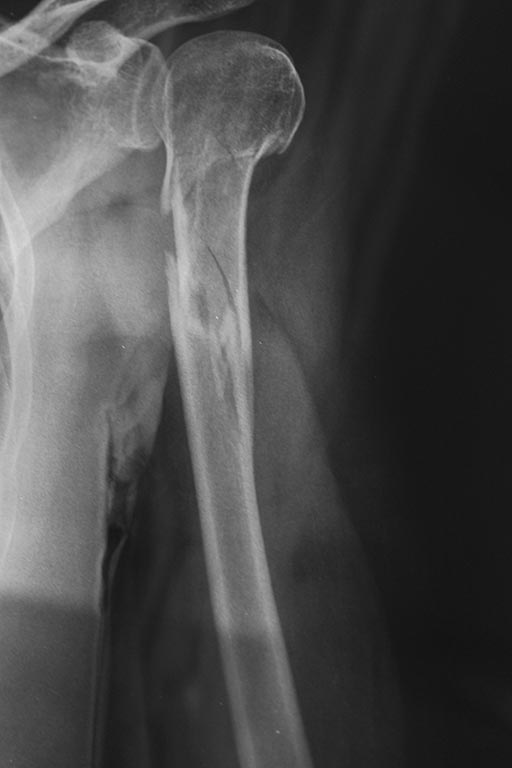

Достаточно было одного этого снимка (тоже пришлось уменьшить и сделать черно-белым.). Конечно, тут длинный PHN (названный T2 более чем годится) самое то.

Более корректной боковой Rg, к сожалению, не получилось.

"Правильным путем идете, товарищи!" В.И.Ленин Закрыто штифтуйте длинным проксимальным (реконструктивным) стержнем.